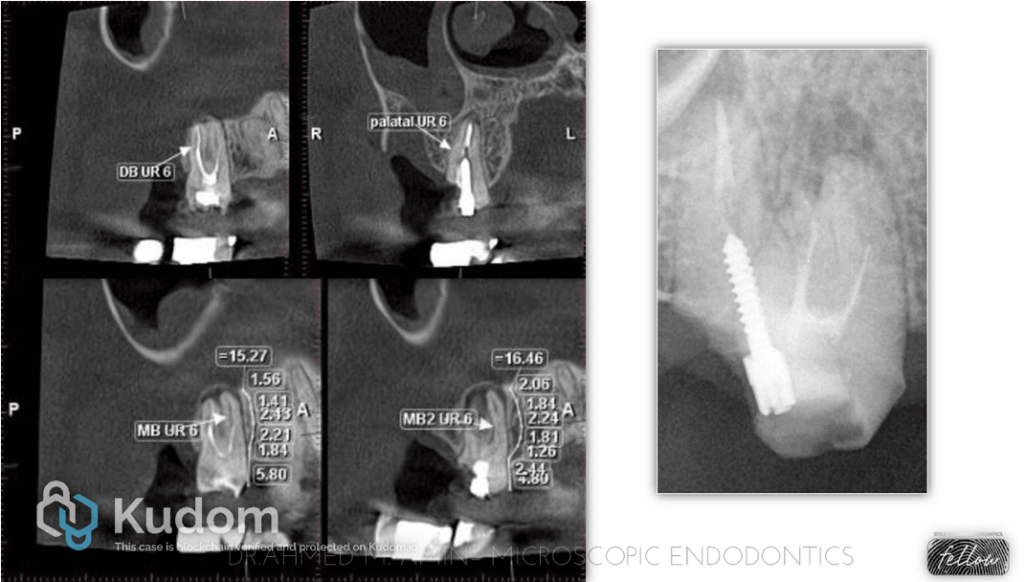

Fig. 1

A 32-year-old male patient presented to my clinic with a badly decayed prepared tooth no. 17, and he insisted on saving it rather than extraction & implant, which was an option.

At first, I’d like to highlight the importance of CBCT for the assessment of such cases to be able to put the best treatment plan for the patient and also to determine the cost of all procedures.

We requested CBCT, and we found 3 roots with 4 canals.

-MB Root had 2 root canals with an isthmus connection and separate apical foramina.

-Missed Mb2 Canal

- A ledge & unextended root canal filling material of the MB root canal